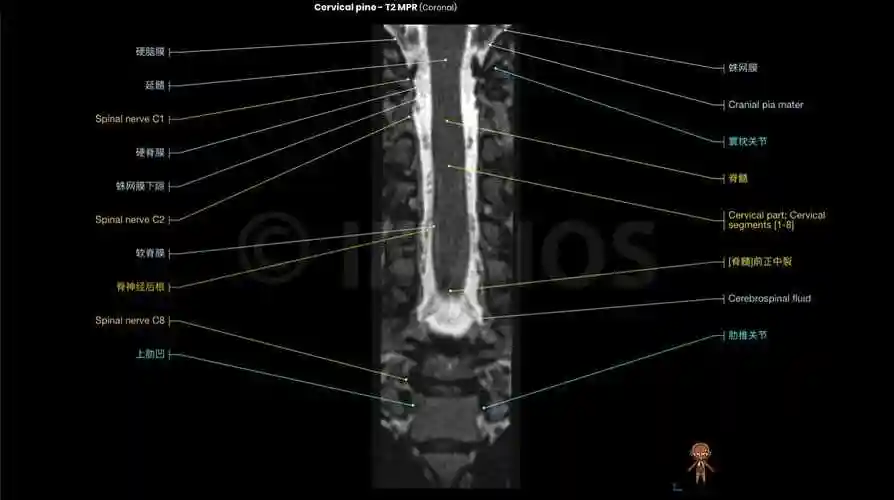

颈椎mri解剖图(轴向,冠状,矢状切片)